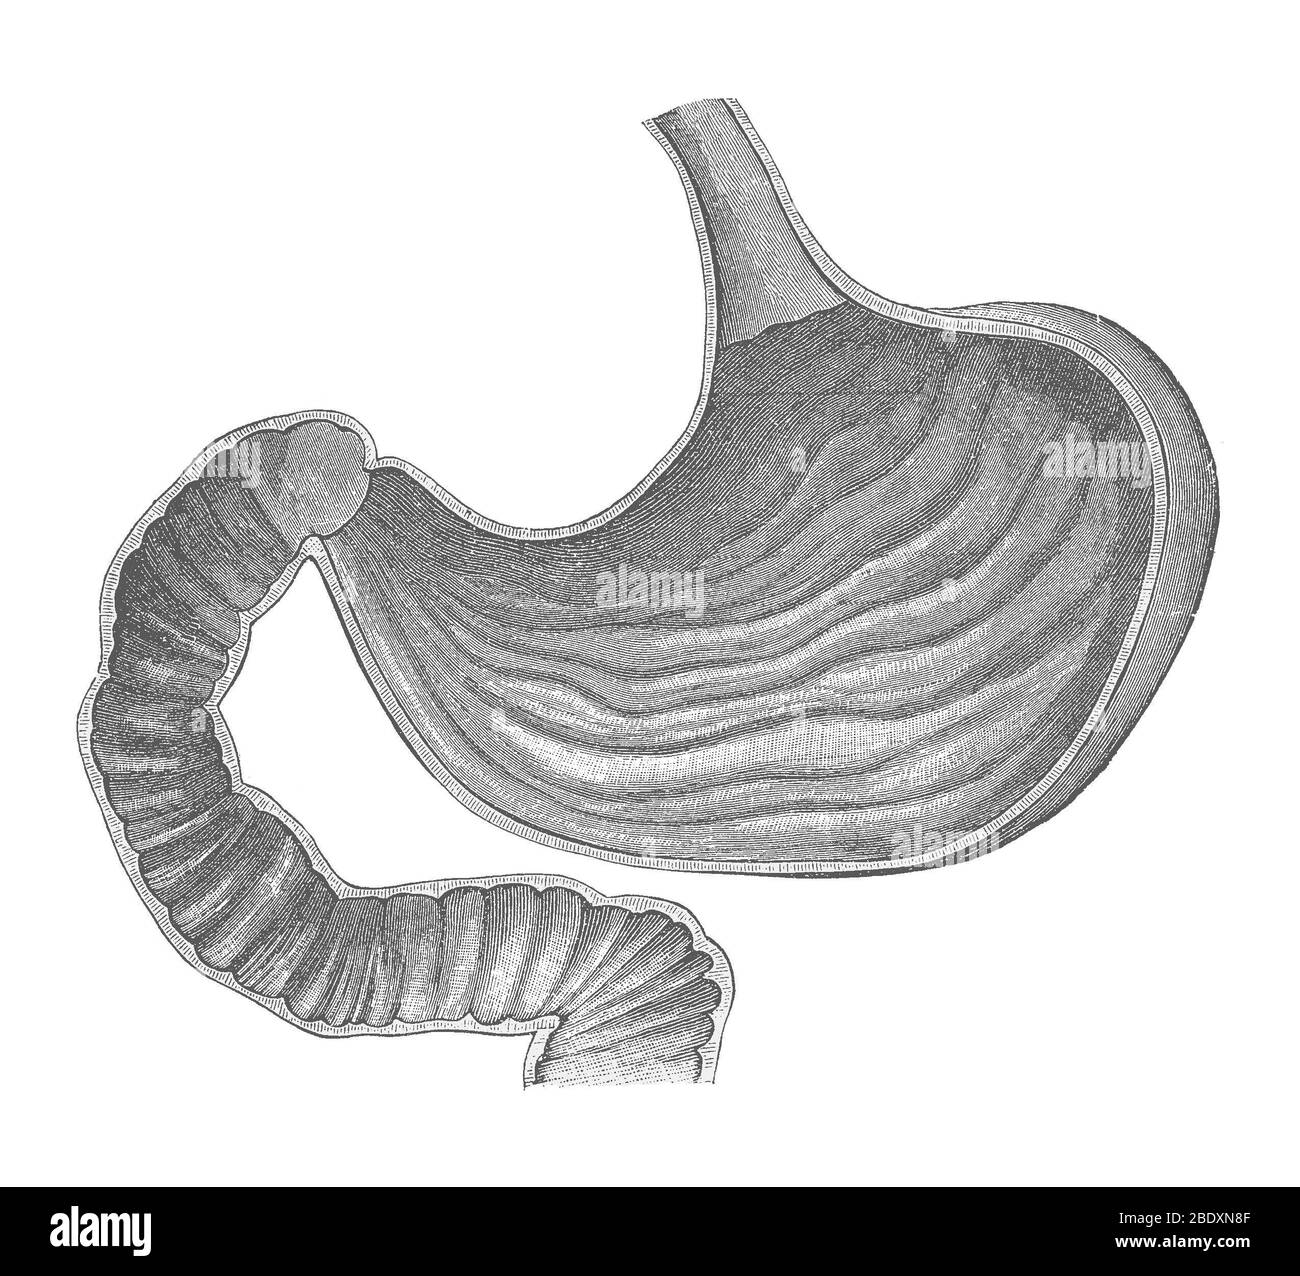

Stomach Stock Photohttps://www.alamy.com/image-license-details/?v=1https://www.alamy.com/stomach-image352785343.html

Stomach Stock Photohttps://www.alamy.com/image-license-details/?v=1https://www.alamy.com/stomach-image352785343.htmlRM2BDXN8F–Stomach